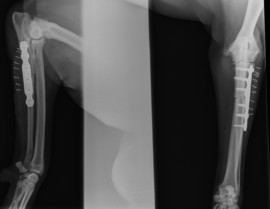

Dirigido y fundado por Alfonso Chico, las 10 personas que componen su plantilla tienen como prioridad mejorar la salud de sus pacientes combinando un trato humano y personalizado con técnicas y equipos de vanguardia. Esto hace del CQV un referente a nivel nacional en el tratamiento de patologías como la displasia de codo, lesiones de rodilla o enfermedades articulares. Por esta razón, diversas empresas y laboratorios buscan frecuentemente su colaboración para estudios clínicos y lanzamiento de productos, y nuestra presencia como ponentes es requerida en numerosos congresos.

- Traumatología y ortopedia. Artroscopia